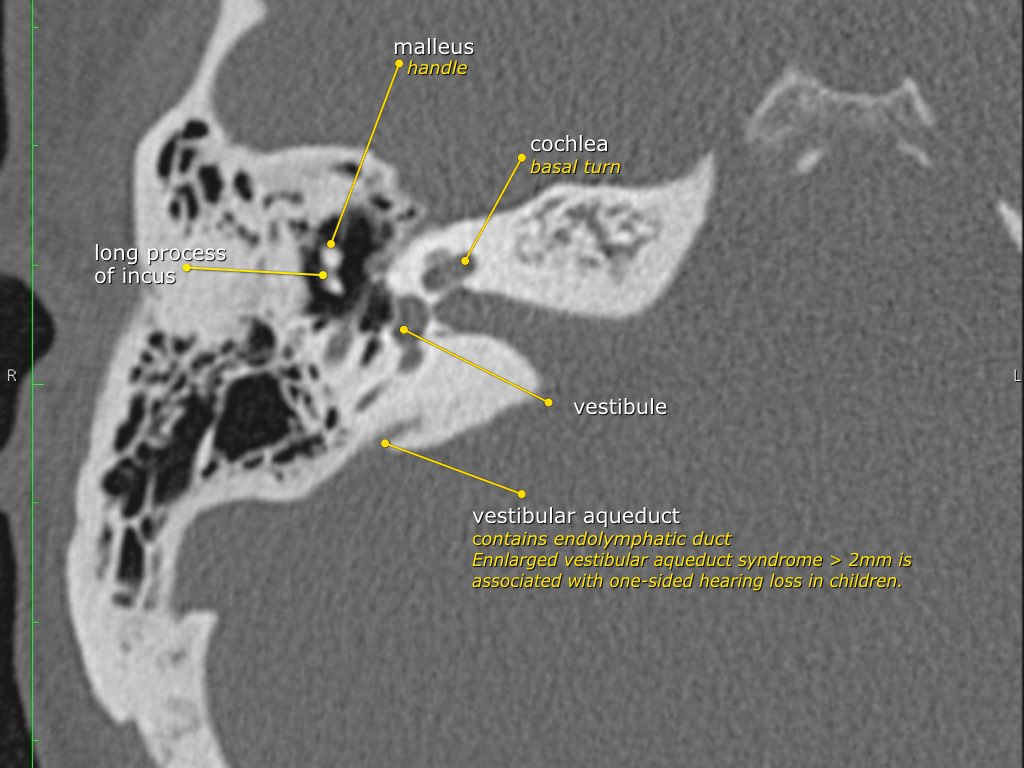

Trong bài tổng quan này, chúng tôi trình bày giải phẫu bình thường trên mặt phẳng cắt ngang (axial) và mặt phẳng cắt đứng ngang (coronal) của xương thái dương thông qua việc duyệt qua các hình ảnh.

Một số cấu trúc được thảo luận chi tiết hơn với trọng tâm là các bệnh lý liên quan.

Giải phẫu xương đá trên mặt phẳng cắt ngang (Axial)

Nhấp vào hình ảnh để phóng to.

Cuộn qua các hình ảnh.

Chuỗi xương con

Trong nhiều hình minh họa, xương đe thường được vẽ kết nối về phía trong với xương búa, tuy nhiên điều này không chính xác.

Trên ảnh tái tạo mặt phẳng coronal bên trái, có thể thấy rõ ràng rằng xương đe nằm ở phía sau ngoài so với đầu xương búa.

Ngành dài của xương đe sau đó chạy xuống dưới và vào trong để tiếp khớp với xương bàn đạp.